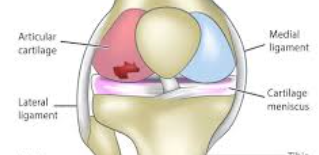

무릎 인대 손상은 주로 외상에 의해 발생하며, 갑작스럽고 예리한 통증이 특징입니다. 반면 연골 손상은 점진적으로 발생하며 둔한 통증의 양상을 보입니다. 인대 손상 시에는 무릎이 흔들리는 불안정감이 뚜렷하지만, 연골 손상에서는 관절 강직감이 더 두드러집니다.

반월상연골파열과의 구별

반월상연골파열은 무릎을 움직일 때 '걸리는' 느낌과 함께 갑작스러운 통증이 나타나는 것이 특징입니다. 특정 자세에서 무릎이 잠기는 증상이 나타나기도 합니다. 관절연골 손상은 지속적이고 점진적인 통증의 양상을 보여 구별됩니다.